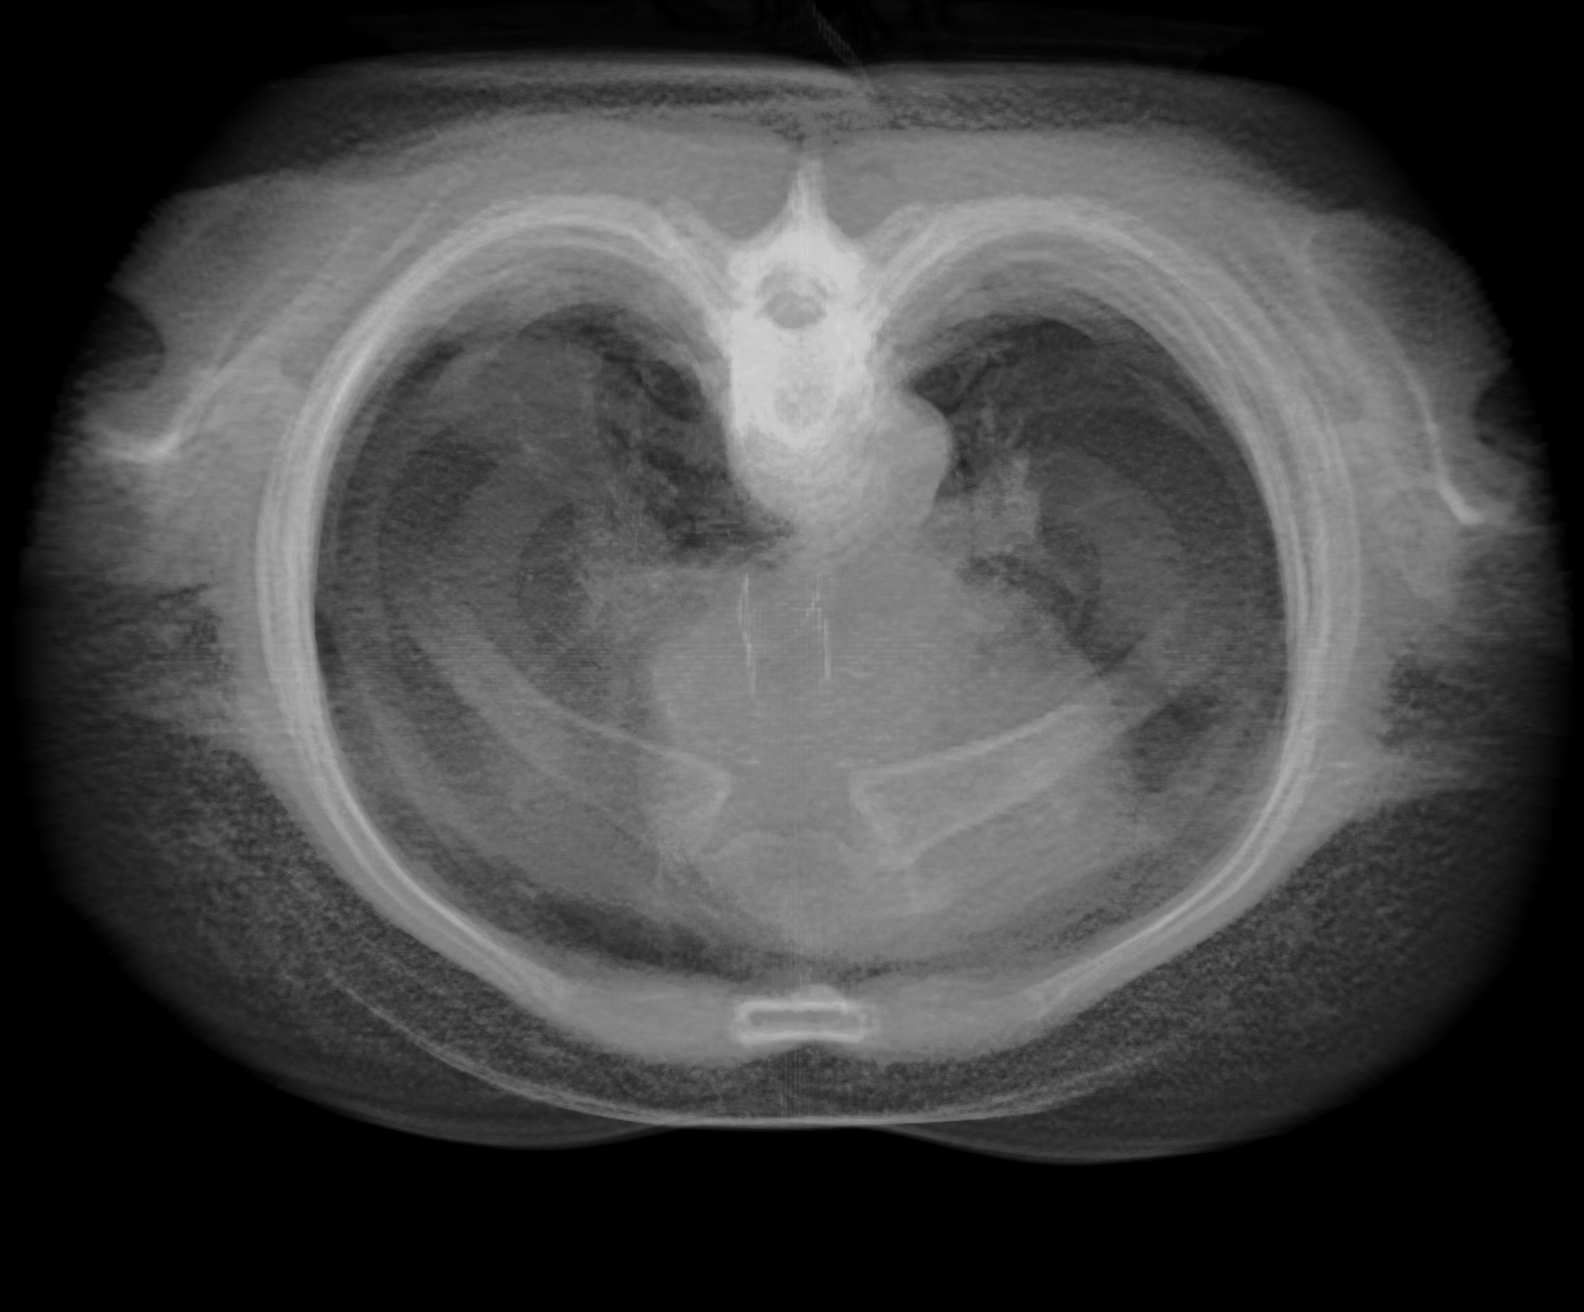

step2-16bit-fb-tex.png (886.8 KB ) - added by Tom Goddard 7 years ago.

Step 2, 16-bit framebuffer and texture

Attachment: step2-16bit-fb-tex.png added

I attached 6 example images of a lung CT scan (folder 4-24533), grid size 512 x 512 x 236, 3d projection rendered with plane spacing minimum along 3 axes, voxel size .576 x .576 x 1.25, so about 500 planes, view along z axis, perspective projection. Step 1 and 2 look quite different with normal 8-bit rendering, but look nearly the same with 16-bit rendering. Both 16-bit framebuffer and 16-bit color/alpha texture contribute have significant effect on the appearance.